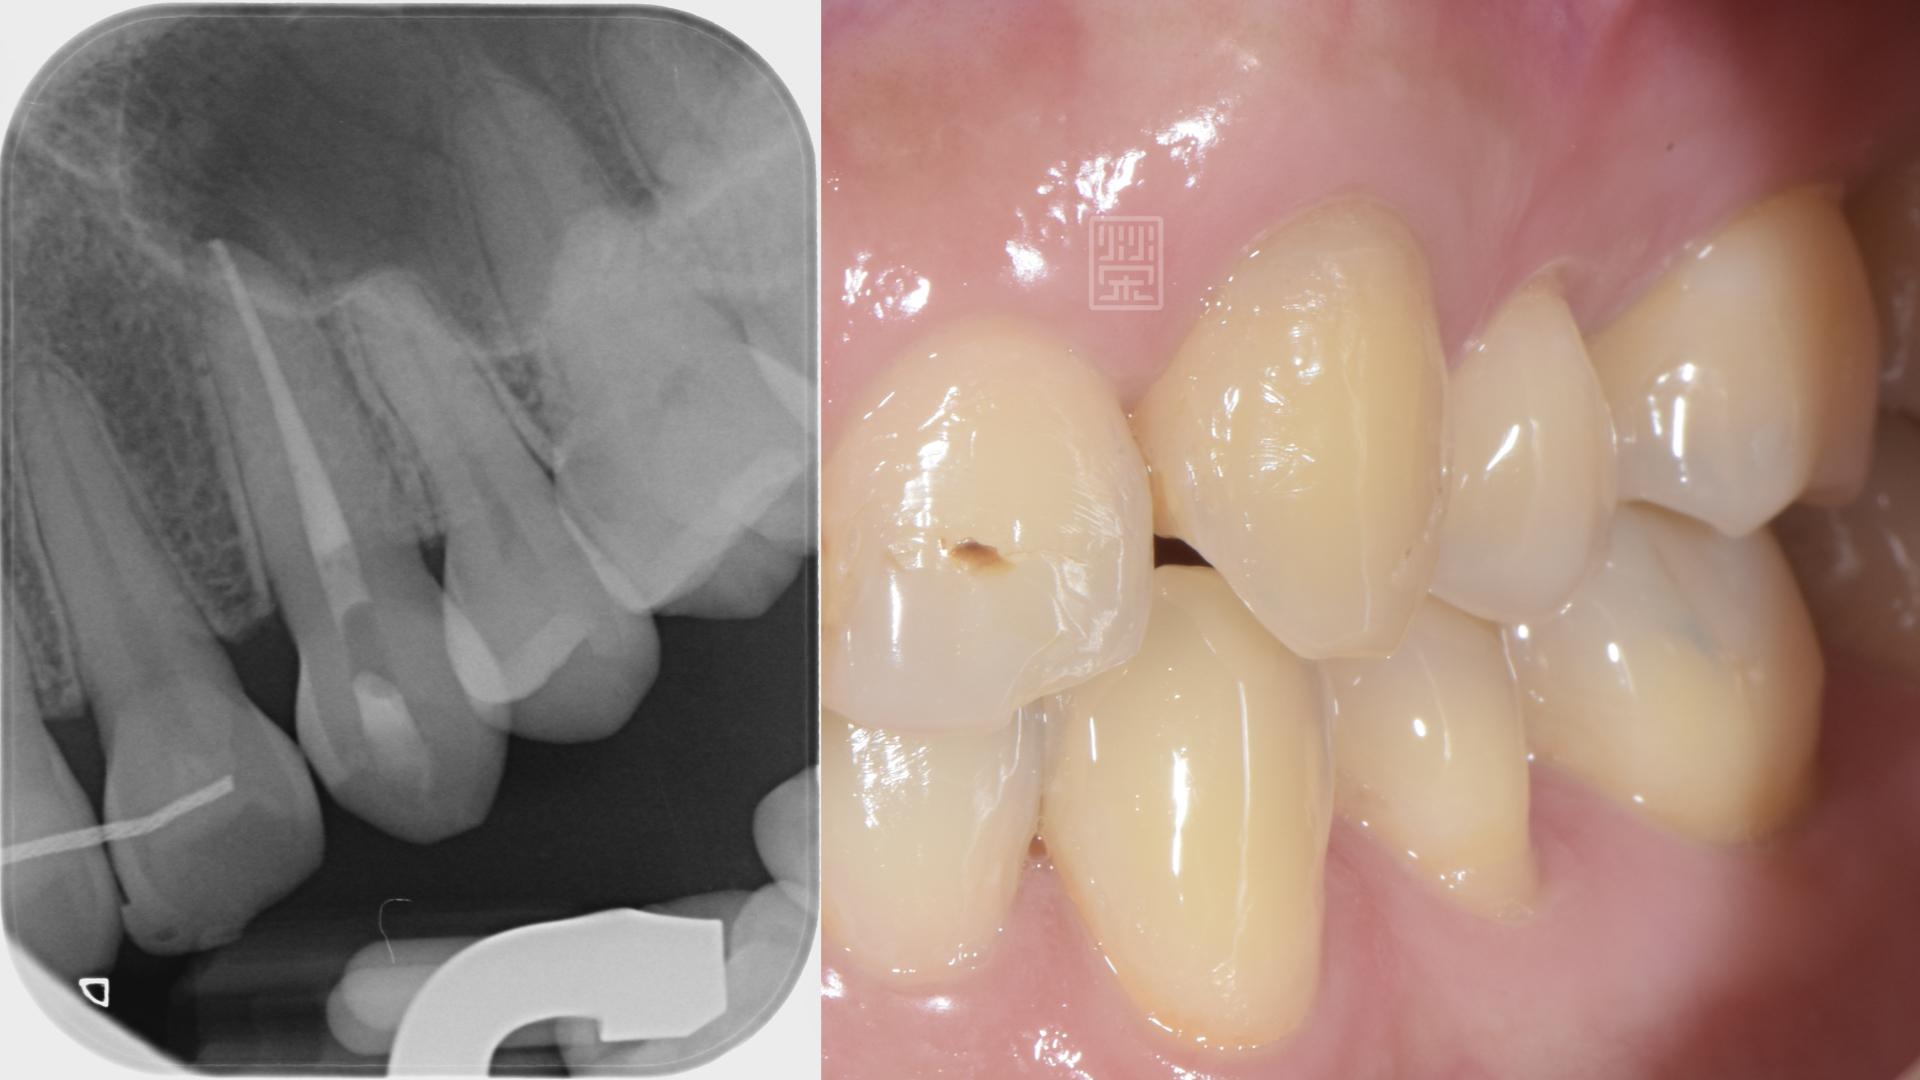

既然已經確定牙齒神經病變壞死,所以將牙髓組織清除,然後做齒內美白,恢復牙齒原本的顏色。

根管治療並且齒內美白